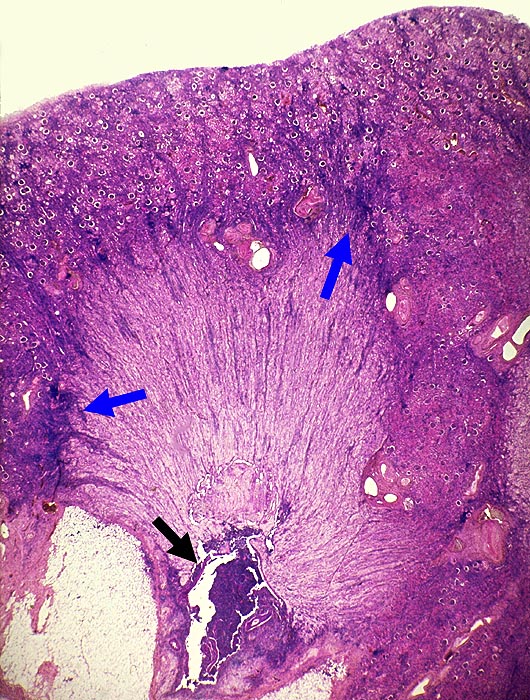

AP/ Analgetikanephropathie

Analgetikanephropathie

Niere

Morphologie